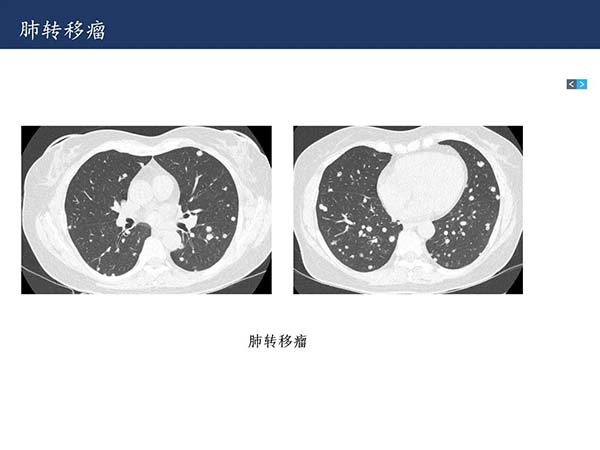

【杨柳科普】肺上皮样血管内皮瘤的影像表现